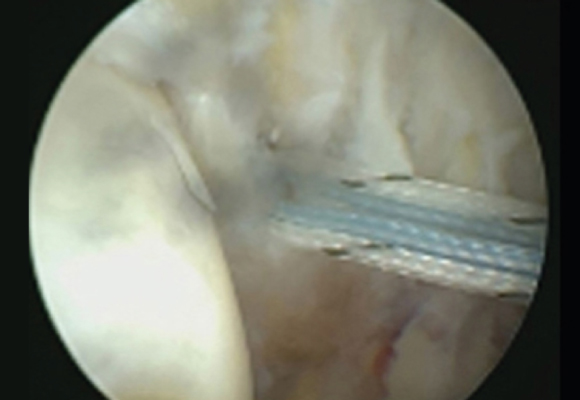

노화된 어깨의 관절낭을 절제해 간격을 넓혀주는 수술 시행

ㆍ환자의 동의를 받은 자료이며, 이미지 사진은 실물과 다를 수 있습니다. (16.09.30)